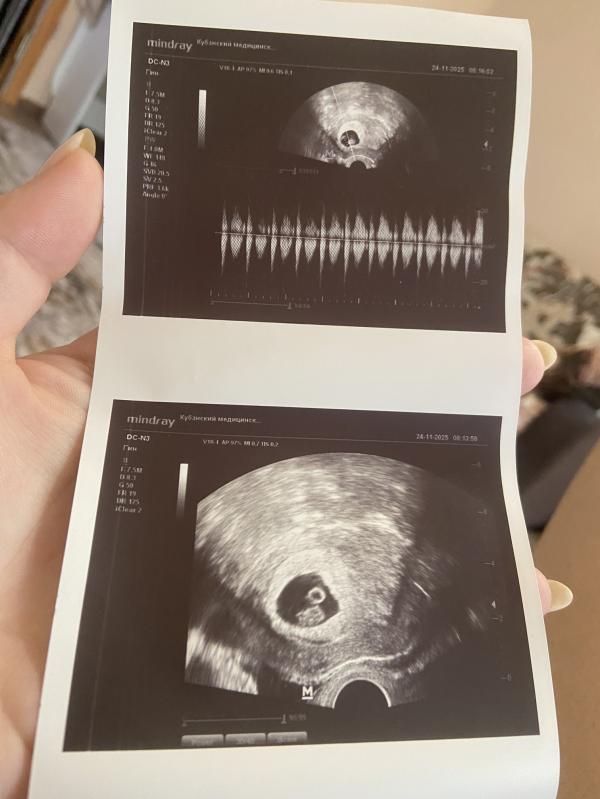

Всем доброе утро❤️ сегодня сходила на узи 😍 Успокоила себя, все хорошо 🙏🏻 Наконец то определила причину своих предыдущих кровотечений - это гематома ( как я и чувствовала ) она маленькая, но надеюсь скоро исчезнет. Всем здоровья 🥰